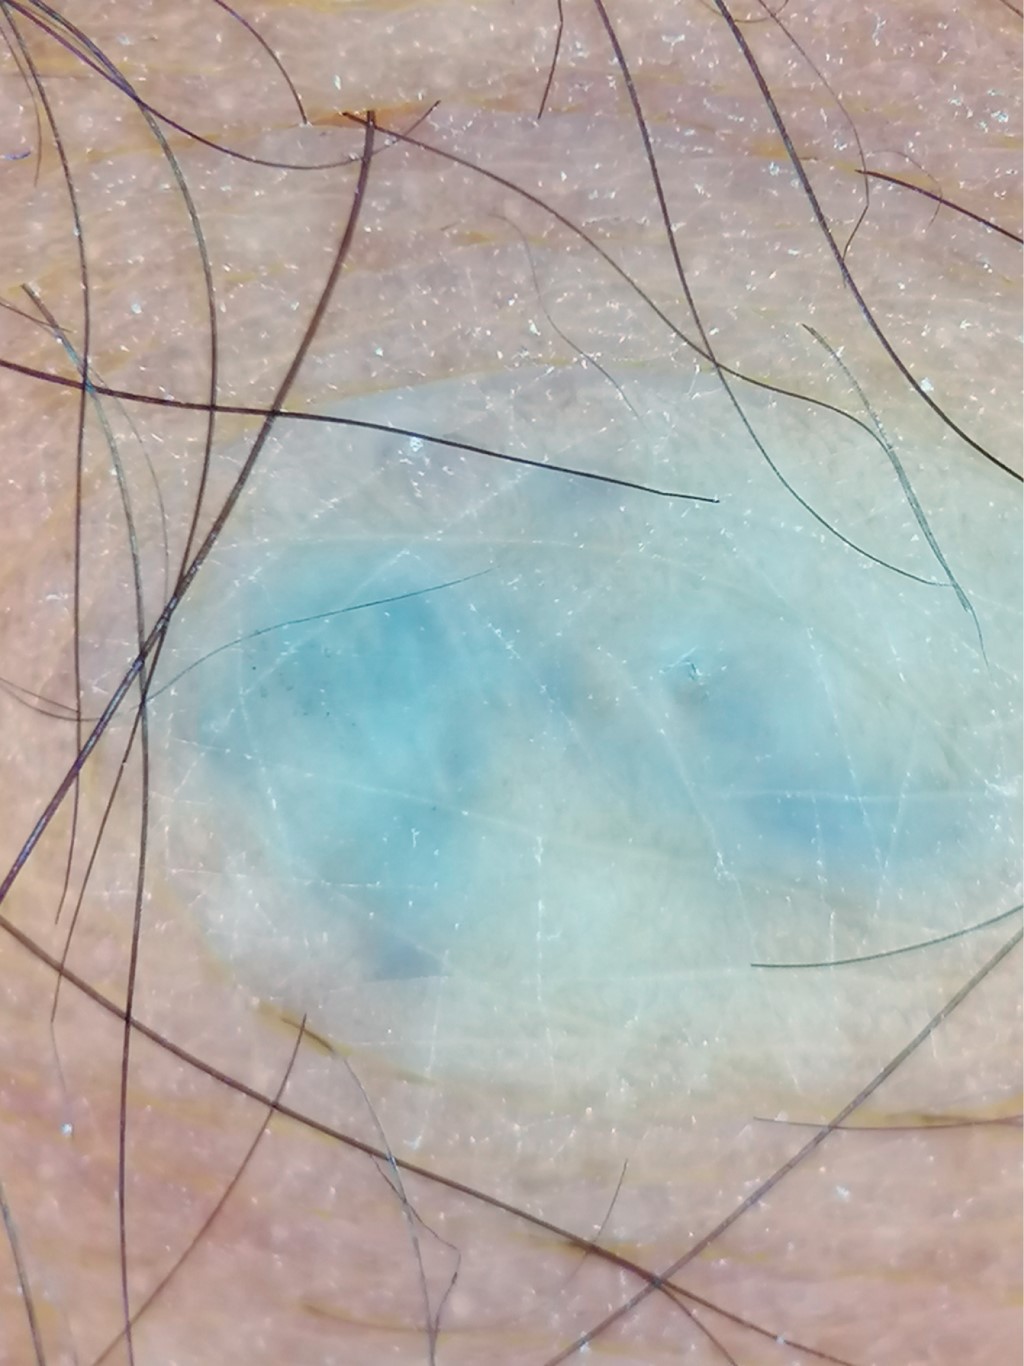

A la dermatoscopía se observan áreas azul violeta sin estructuras, rodeadas por un halo blanquecino (Figuras 3 y 4).

La dermatoscopía es una herramienta útil y accesible al momento de llevar a cabo la exploración física. En la literatura no se han descrito muchos casos acerca de las características dermatoscópicas del TGE, solo cuatro casos, en donde describen áreas violáceas homogéneas sin estructuras celulares, rodeadas de un halo blanquecino, y en otros casos presencia de reticulado fino telangiectásico y zonas azul grisáceas mal definidas.7,11-13

Figura 3

Figura 4